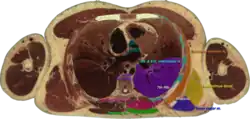

![]() Cross section #1428 of the Visible Human Male showing the structures of the triangle of auscultation | |

It has the following boundaries:

- medially, by the inferior portion of the trapezius

- inferiorly, by the latissimus dorsi

- laterally, by the medial border of the scapula

The superficial floor of the triangle is formed by the lateral portion of the erector spinae muscles. Deep to these muscles are the osseous portions of the 6th and 7th ribs and the internal and external intercostal muscles.